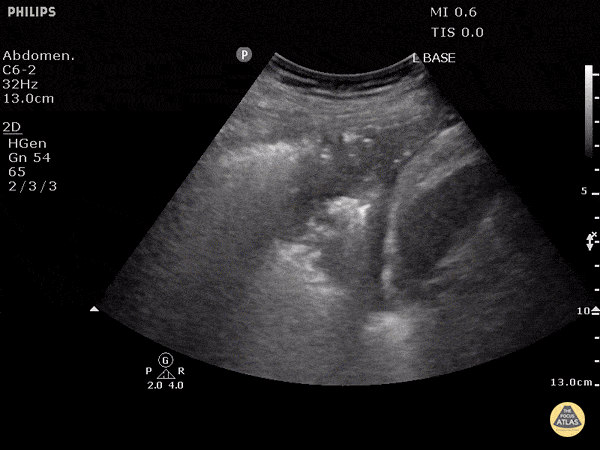

Pulmonary - Compression Atelectasis

The left lung base can be seen with some b-lines indicating atelectasis, with trace pleural effusion. Dr. Justin Bowra et al.